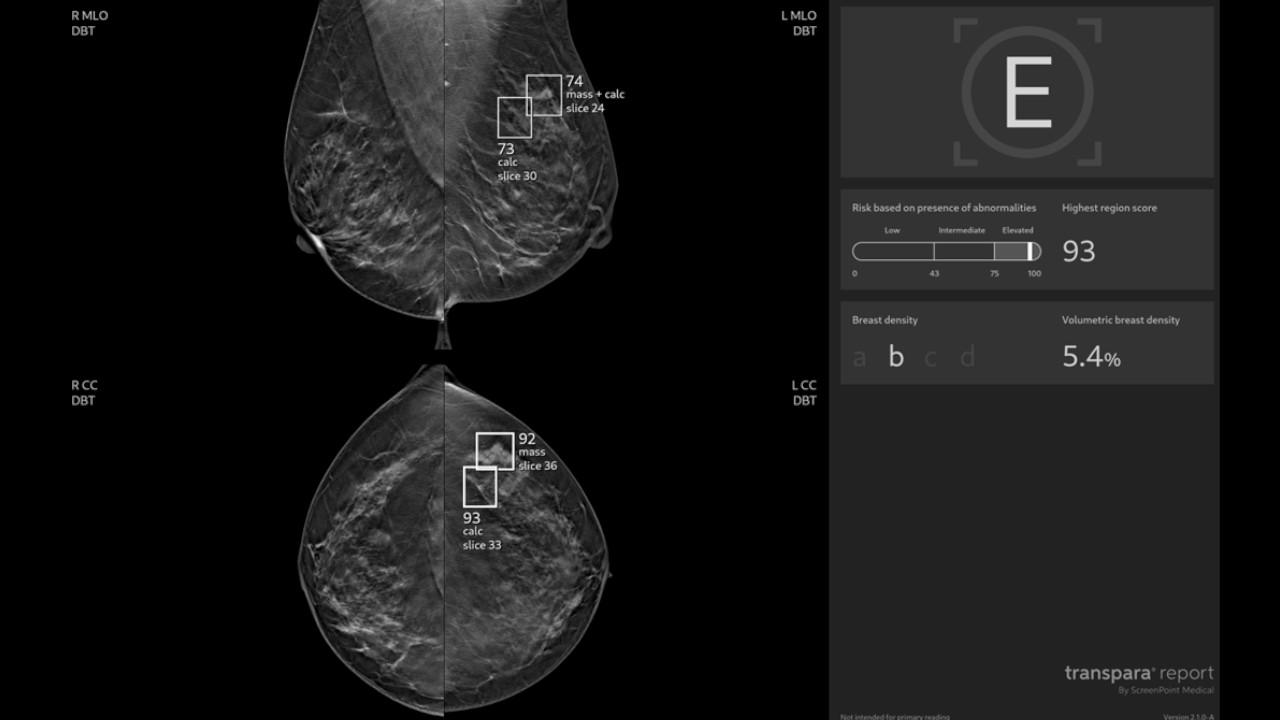

- Improved Diagnostic Accuracy: Enhances mammography readings up to 10% to better detect breast cancer.1

- Efficiency: Streamlines workflows and reduces radiologists’ reading workload by 33%.2

- Patient Outcomes: helps to reduce unnecessary biopsies and supports personalized care.3